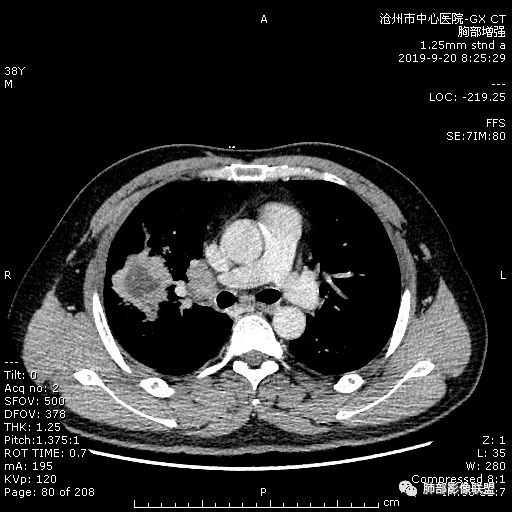

年轻男性,咳嗽2月,痰中带血,胸痛,炎症指标稍高,肿标正常。影像,右肺上叶不规则团块影,浅分叶,伴边界不清磨玻璃影,从外周向内分布,局部胸膜增厚,病灶中央坏死,坏死边界尚清,空洞形成,空洞内壁光滑;考虑炎性肉芽肿性病变,结核可能,鉴别恶性肿瘤及真菌感染。病灶分布特点不考虑隐球。

右肺上叶不规则病灶,密度不均,有分叶,边缘不清,中央有坏死,坏死壁尚光滑,增强壁有强化,病灶有外朝内,整体收缩为主,慢性病程,考虑炎性病变,肺脓肿或者结核,淋巴结肿大,支气管截断,胸膜脂肪间隙变窄,加个鉴别恶性肿瘤。

中年男性,咳嗽2月,伴胸痛8天,少许痰血,无发热中性粒明显增高,低氧,肿标不高,右肺上叶不规则实性肿块,深分叶,局部凹陷呈月牙铲改变,多坏死,多空泡,前段支气管分支似见堵塞,2R、4R、10R和7区淋巴结肿大。考虑肺癌可能,建议支气管镜活检

晨读:右肺上叶不规则团块,深分叶,膨胀为主,有部分收缩,叶间裂牵拉上移,内多液化坏死,有支气管扩张,右肺上叶大支气管近端通畅,远端堵塞,说明肿块来源于外周,纵隔及右肺门淋巴结肿大,胸膜糊墙为主,年轻人,肿标不高,炎性指标高,综合考虑炎性肉芽肿放前面脓肿,结核,肿瘤放后面。

中年男性,咳嗽2月病史伴胸疼。白细胞及中性粒细胞高。右上肺团块影,边缘平直内收,与胸膜宽基底相连,胸膜肥厚,肿块内多灶性坏死,有空泡征,支气管进入,走行自然,近端有阻塞,考虑感染性疾病,肺脓肿。但是有深分叶,鳞癌合并感染也不排除。

3.ct表现:肺脓肿可呈结节状或团块状,有时呈不规则形,气道来源肺脓肿常单发,血行来源常多发,边缘模糊,部分病灶周围可见片状肺实变及磨玻璃影;病灶中央为液化坏死区,若脓肿与支气管相通,脓液排出可形成空洞,空洞内可形成液平;急性肺脓肿内壁多不规则;慢性肺脓肿洞壁较厚,一般不规则或形成多房空洞:CT增强扫描空洞壁可见强化,空洞壁为纤维肉芽组织,呈典型的环形强化;慢性肺脓肿周围可有较广泛的纤维索条影,可伴支气管扩张.肺

气肿或胸膜增厚表现。

今天病例坏死周围也可以看到明显强化的脓肿壁,只是局部脓肿壁不规则模糊,部分脓肿壁规则清楚。